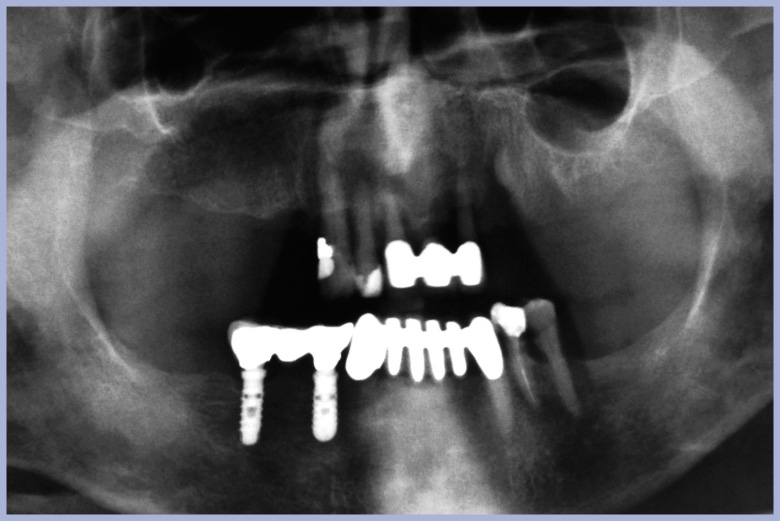

Si montano i denti e si avvita poche ore dopo il posizionamento degli impianti la protesi “All-on-four” sui monconi per protesi avvitata (Figg. 9, 10).

L’ortopantomografia di controllo immediata conferma il corretto posizionamento degli impianti, dei monconi e della protesi (Fig. 11).

- Figg. 9, 10 – Protesi “All-on-four” posizionata in bocca

- Fig. 10

- Fig. 11 – Ortopantomografia post intervento